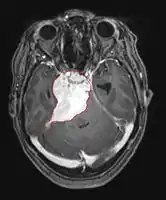

• MRI

• Preferred imaging because it can show dural origin

• Dural tail sign seen in about two-thirds: characteristic marginal thickening that tapers peripherally along the dura

• Isointense on T1, hyperintense (usually homogeneously) on T2, strong enhancement with IV contrast